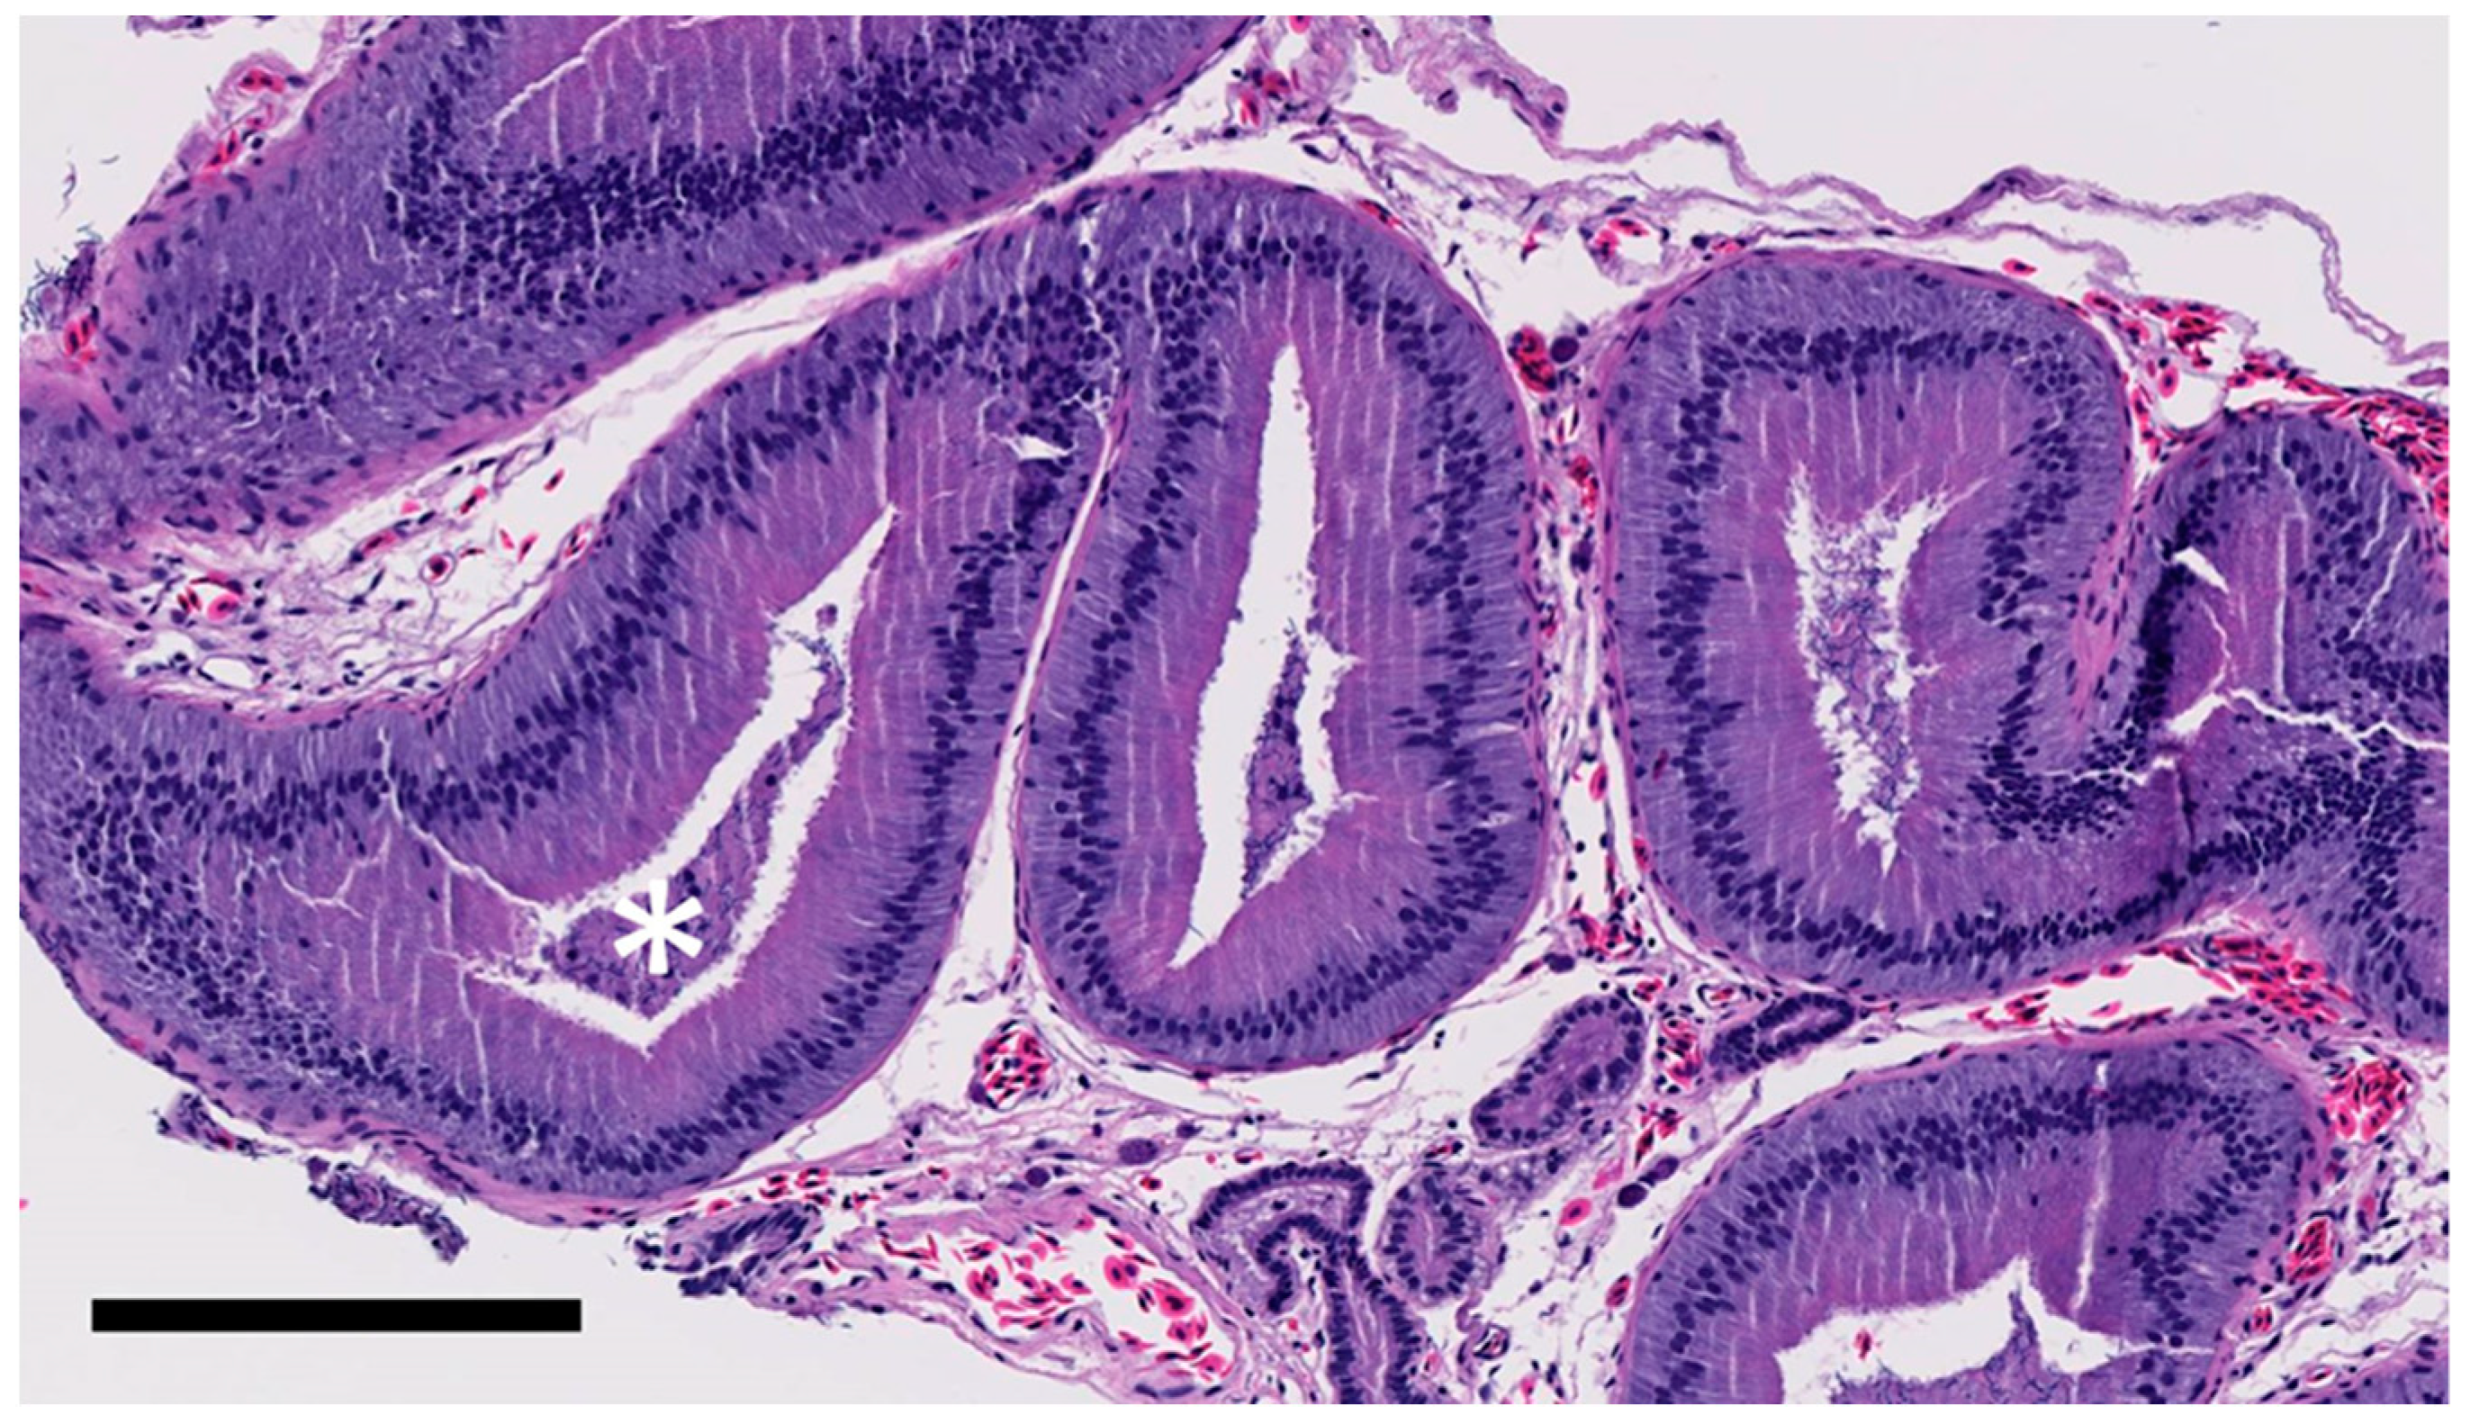

The testicles and epididymides were fixed in 10% neutral buffered formalin, routinely processed, and embedded in paraffin, and 5 μm sections were stained with hematoxylin and eosin for histological analysis. Germ cell identification was performed under light microscopy by reviewing five sections of seminiferous tubules per animal. For micrometric measurements, the slides were scanned using a digital slide scanner (Nanozoomer C9600-02, Hamamatsu Photonics, Hamamatsu City, Japan). The measurements were taken using Aperio ImageScope software (Leica Biosystems, Buffalo Grove, IL, USA). Five measurements were used to define the diameter of the epididymis; ten measurements to define epididymal epithelial height; twenty measurements to define the diameter of the seminiferous tubules; five measurements to define the numbers of interstitial cells; ten measurements to define the interstitial cell nuclear diameter from each animal. The numbers of interstitial cells were counted from triangular interstitial areas formed by three sections of seminiferous tubules. For the diameter of seminiferous tubules, diameters of round sections, or short axes of elongated sections were measured. Intraepithelial secretory granules of the epididymal epithelial cells, intraluminal spermatozoa in the epididymis, interstitial cell cytoplasm, and vacuolation in the testes were graded from 1 to 3. All samples were reviewed by the same author (JL).

There was a significant difference in the seminiferous tubule diameters (F = 4.4, p = 0.025) by treatment group, with PMSG treated gecko seminiferous tubule diameters being higher (mean: 229.9 µm, SD: 16.8, min–max: 200.5–264.9) than saline controls (mean: 205.6, SD: 40.9, 135.1–255.6). There were no significant differences in epididymal diameter (F = 0.9, p = 0.356), interstitial cell nuclear diameter (F = 0.07, p = 0.785), interstitial cell number (F = 0.629, p = 0.436), or epididymal epithelial height (F = 2.5, p = 0.067) between saline and PMSG treated geckos, although epididymal epithelial height approached significance. There was a significant difference in epididymal intraluminal spermatozoa (z = −1.6, p = 0.045) between treatment groups, with abundant spermatozoa found in 78.6% (11/14) of PMSG treated geckos and only 40% (2/5) of saline treated geckos. There were no significant differences in secretory granule content (Z = −0.394, p = 0.347) between treatment groups. There were no significant differences in cytoplasmic vacuolization (Z = −2.43, p = 0.417) or interstitial cell cytoplasm (Z = −2.57, p = 0.417) between saline and PMSG treated geckos. There was no significant difference in the presence of mature spermatozoa in the post-surgical testicles based on sample section reviewed (X2 = 3.7, p = 0.491) or treatment group (X2 = 3.9, p = 0.142). Mature spermatozoa were found to be abundant (80.8%) in the post-surgical testicles; fewer samples were found to have moderate (10.8%), few (6.7%), or absent (1.7%) mature spermatozoa. Spermatogonia, round spermatids, elongate spermatids, and primary spermatocytes were present in all three groups of geckos.

The histological findings of this study confirm that PMSG had an impact on spermatogenesis, but did not significantly impact steroidogenesis. The measurements collected in this study, including the diameters of the epididymis and seminiferous tubules, presence of germ cell developmental stages, epididymal epithelial heights, numbers of epididymal intraepithelial secretory granules, numbers of interstitial cells, and abundance of interstitial cell cytoplasm and cytoplasmic vacuoles, were based on previous histologic descriptions in other lizards [24,30,60]. Seminiferous tubule diameters were larger in animals receiving PMSG compared with controls. Additionally, intraluminal spermatozoa in the epididymides were nearly twice as abundant in animals receiving PMSG (Figure 5) compared to saline (Figure 6). However, there were no significant differences in the interstitial cell numbers or nuclear diameters, nor the epidydimal epithelial heights between the saline and PMSG treatment groups, suggesting that no additional Leydig cell hyperplasia or hypertrophy took place in animals receiving PMSG. The findings of this study are in contrast to others in reptiles that directly measured testosterone concentrations and testicular histology following the administration of PMSG [19,21,23,24,30]. In these previous studies, significant increases in circulating testosterone were measured following PMSG administration, and histology of the testes and epididymides noted an increase in the interstitial cells, suggesting probable androgen production. However, in these studies, sampling was conducted during the quiescent phases of reproduction for each species. The breeding season of leopard geckos in the Northern Hemisphere begins as early as January and extends to late September [40]. However, despite this study taking place firmly within the proposed non-breeding phase for this species, the animals used in this study possessed high mean baseline testosterone concentrations averaged over the three months of the study (79.4 ng/mL). Based on these results, it is possible that the leopard gecko follows a three-phase reproductive cycle, similar to those exhibited in the Caspian bent-toed gecko (Cyrtopodion caspium) and the house gecko (Hemidactylus flaviviridis). However, it is also possible that, similar to the common gecko (Hemidactylus brooki), leopard geckos may be spermatogenically active throughout the year [64]. The seasonally breeding Caspian bent-toed gecko was described as having three phases of spermatogenesis: the active, transitional, and inactive phases [65]. Additionally, house geckos possess a three-phase reproductive cycle, characterized by quiescent, recrudescent, and active phases [66]. The quiescent phase of the reproductive cycle in the house gecko was characterized by flaccid, small testes, no spermatogenic activity, and low plasma steroid concentrations, while the recrudescent phase, occurring in September–October, demonstrated increasing testicular mass, increased primary and secondary spermatids, a rise in plasma steroid concentrations, and increased steroidogenic factors in the Sertoli and Leydig cells. The active phase, occurring in November–May, exhibited large numbers of mature spermatozoa in all sections of the epididymis, peak plasma steroids, and fully developed ultrastructural steroidogenic features [66]. Conversely, previous findings in common geckos from India determined that, although there was significant variation in testicular mass between different months of the year, the testes were spermatogenically active throughout most of the year, with the exception between June and September, during the wet season, where few animals possessed abundant spermatozoa [64]. Smaller sizes of Leydig cell nuclei were also observed from May–August in these geckos, suggesting reduced androgen output during low spermatogenic activity. Lizards, in general, exhibit prenuptial spermatogenesis [64], with spermatozoa being produced prior to mating. Thus, PMSG likely did not further increase testosterone production during this period of early spermatogenesis since it was already elevated naturally during this phase, further supporting the idea that leopard geckos likely follow a prenuptial pattern of reproduction. Based on results obtained in the current study, the authors propose that the leopard geckos were either in the late stages of the recrudescent phase of spermatogenesis, or they may exhibit more continuous spermatogenesis throughout the year, and PMSG acted to further stimulate spermatogenesis in these animals. Ultimately, extending sample collection from January through September will be needed to confirm one of these theories.